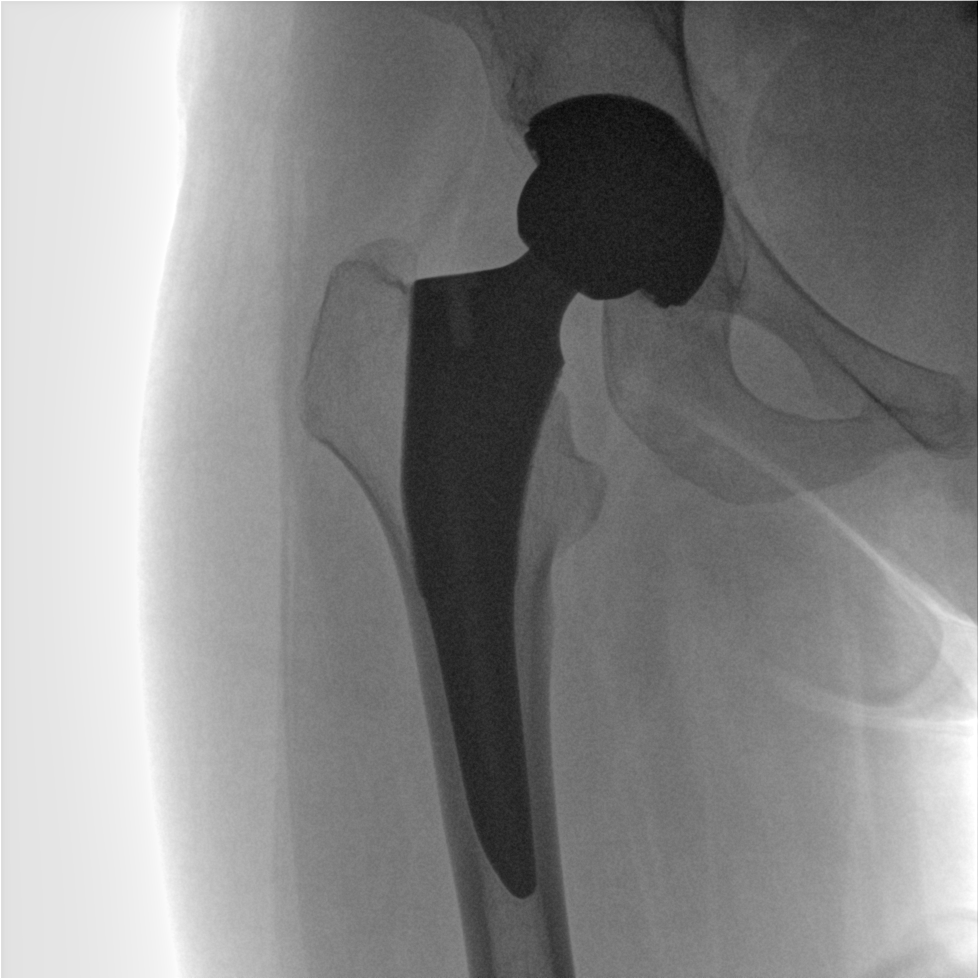

術(shù)中三維成像和橫斷面圖像提供多角度的手術(shù)診斷信息,輔助醫(yī)生進行術(shù)中評估判斷,諸如骨折復位情況和內(nèi)植入螺釘?shù)某叽绾臀恢茫o助手術(shù)更好地完成。

提供更大的術(shù)中三維成像視野,采集更多圖像信息,可一次拍全全段頸椎、全段腰椎、七節(jié)胸椎、雙側(cè)骶髂關(guān)節(jié)、股骨頭及單側(cè)盆骨。